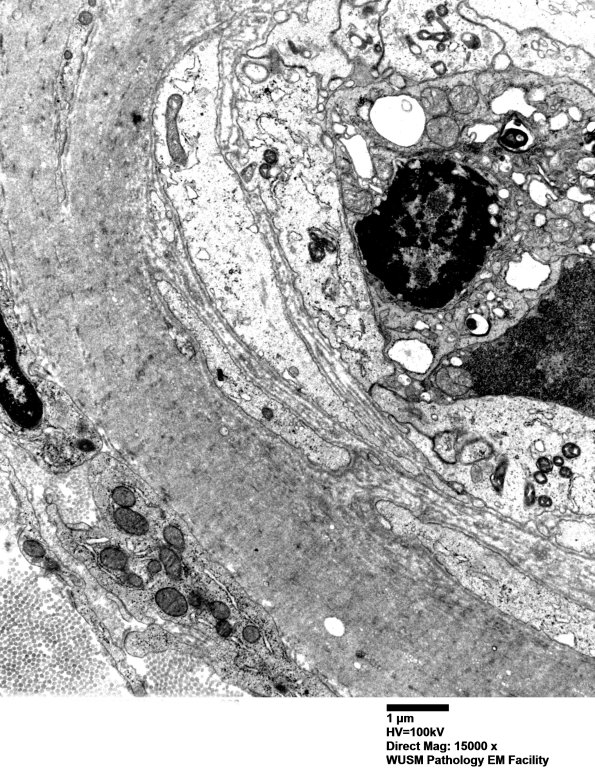

This vessel shows purely collagenous thickening of the endothelium. (electron micrographs) ---- Comment: C5b9 was deposited in endoneurial microvessels by immunohistochemistry. Clinically and immunohistochemically this case merits the diagnosis of HIEM.